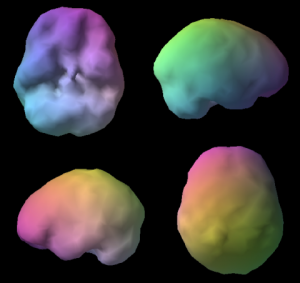

Wówczas pokazuję im skan mózgu SPECT. Badanie to ma na celu zobrazować ukrwienie fotografowanego organu.

- Pierwsze zdjęcie to zdrowy, dobrze funkcjonujący mózg człowieka.

- Zdjęcie drugie to mózg szesnastolatka, który od dwóch lat regularnie pali marihuanę.

Te puste miejsca nie są fizycznymi dziurami, do których można włożyć palec, ale są to miejsca niedokrwione. Taki stan mózgu bez wątpienia świadczy o jakiejś „utracie zdrowotnej”.

Podczas moich warsztatów z młodzieżą pt. „Twój czas” zestawiam te dwa zdjęcia i zadaję pytanie „który mózg wybierasz?”

Wszyscy, i zwolennicy i przeciwnicy i ci, którzy nie mają zdania, odpowiadają „ten pierwszy”. To naturalne, że wszyscy chcemy być zdrowi i szczęśliwi. Jednakże ten mózg to mózg, na który trzeba sobie zapracować i pracować systematycznie, by utrzymać go w dobrej kondycji. Osoba paląca może „nie dźwignąć” takiego ciężaru, by uzyskać taki stan „umysłu”. Szczególnie kiedy zaczyna palić wcześnie. Okres nastoletni to okres bardzo progresywnego rozwoju i zmian zachodzących w mózgu. Niewłaściwe „używanie” tego organu może powodować konsekwencje na resztę życia. Palacz marihuany może „nie udźwignąć” wyzwania, by wykorzystać potencjał swojej pierwotnej natury, z którą przyszedł na świat. Może już nigdy nie wyćwiczyć tego najważniejszego „mięśnia”, od którego zależy jakość naszego życia.

Zdjęcia SPECT mózgu pochodzą https://www.amenclinics.com/